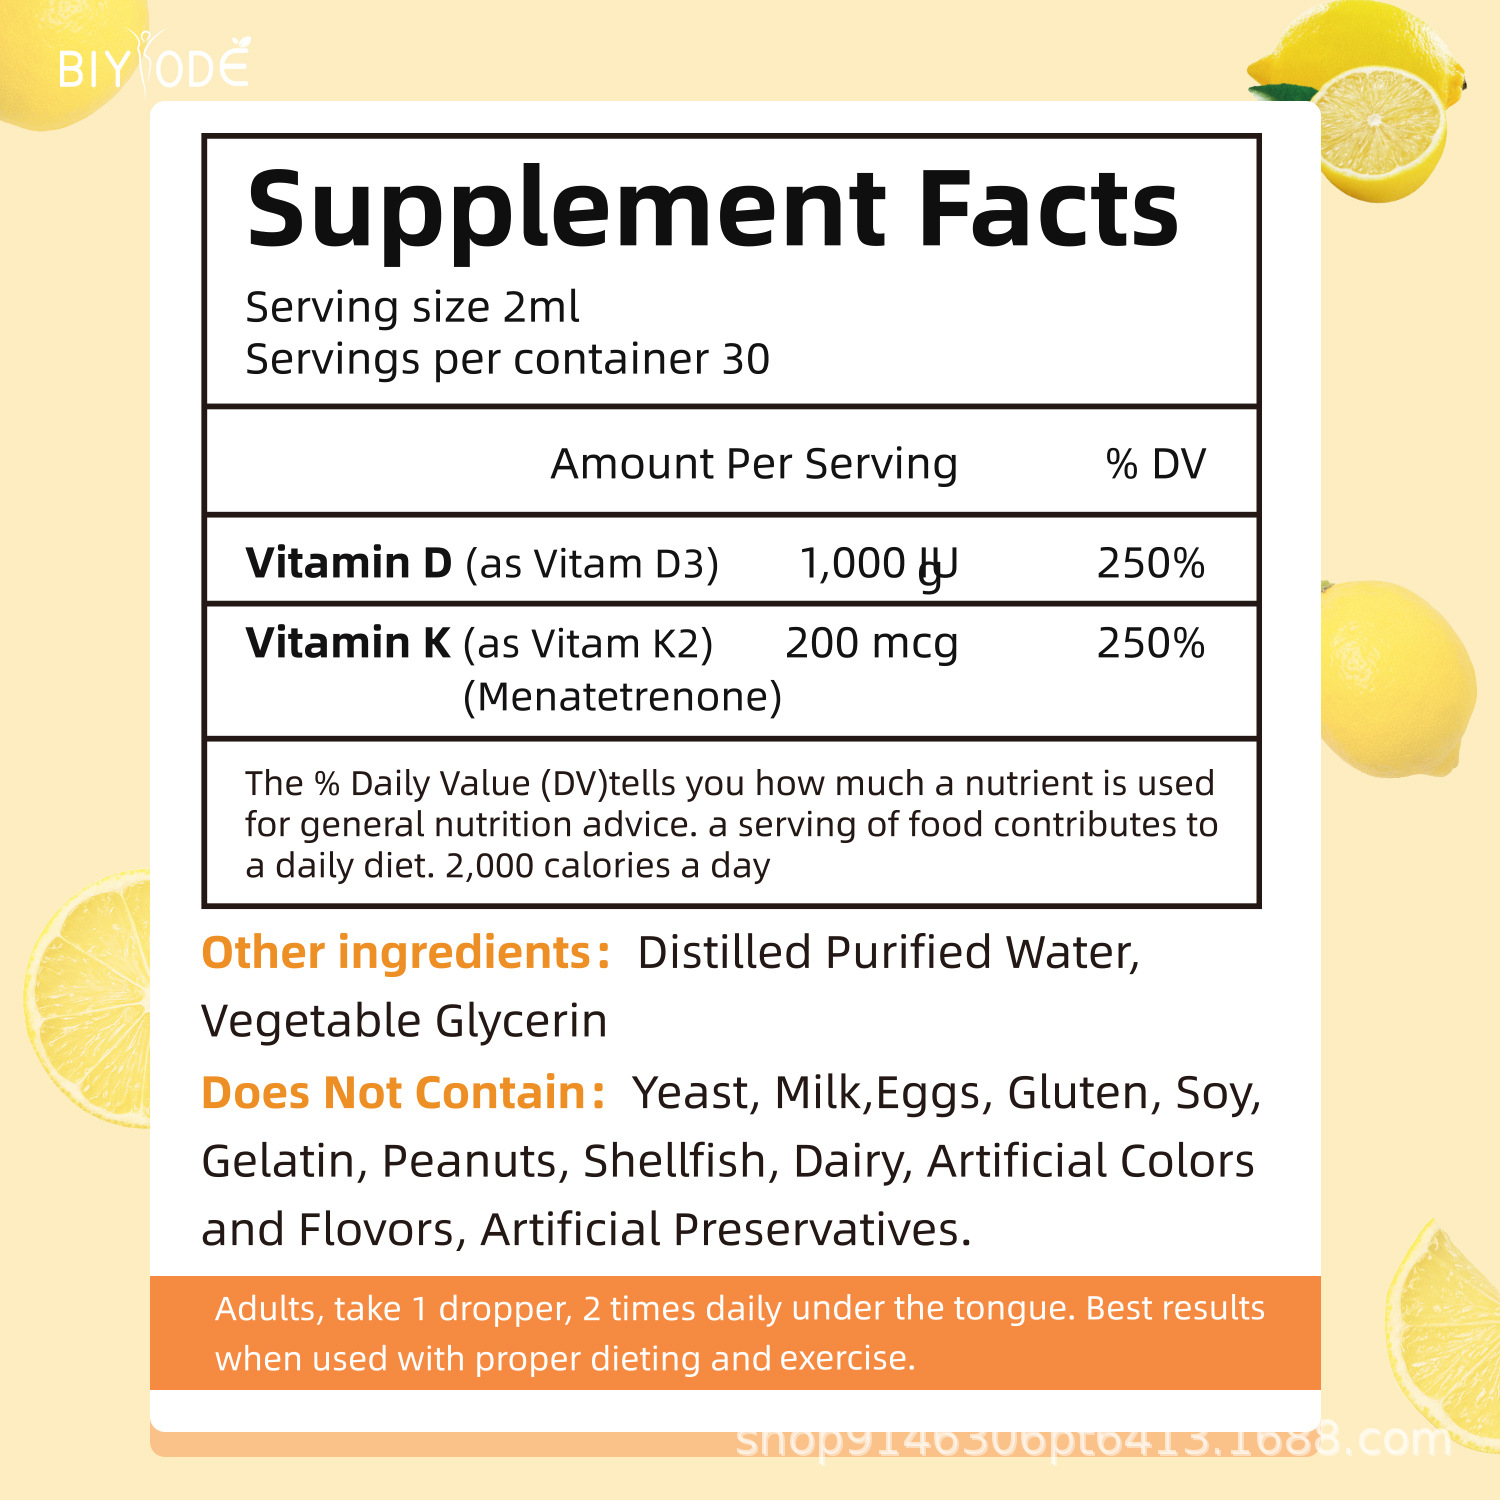

Product Name: d3+k2 Drops

Net content: 60ML

Type: Drops

Main raw material :d3k2